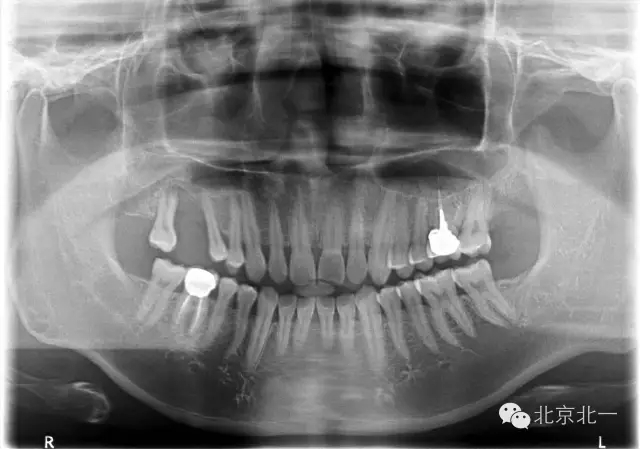

患者,男,30歲,右側(cè)上頜后牙區(qū)缺失,咨詢種植。

檢查:15、16 缺失。17三度松動(dòng)。

CBCT顯示,骨寬度可,骨高度不足,月3mm。頜間距離增大。

診斷:牙列缺損,牙周炎

圖二:手術(shù)前全景片